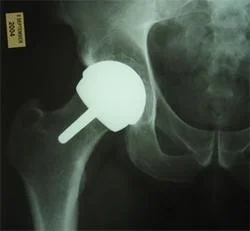

Total Joint Arthroplasty:

-

Replacing the native joint with prosthesis

Indicated:

- Old patient with deformed, stiff & painful joint.

Contraindication:

- Young active patients

- Infected joint

- Neuropathic joint

Used:

- All joints.